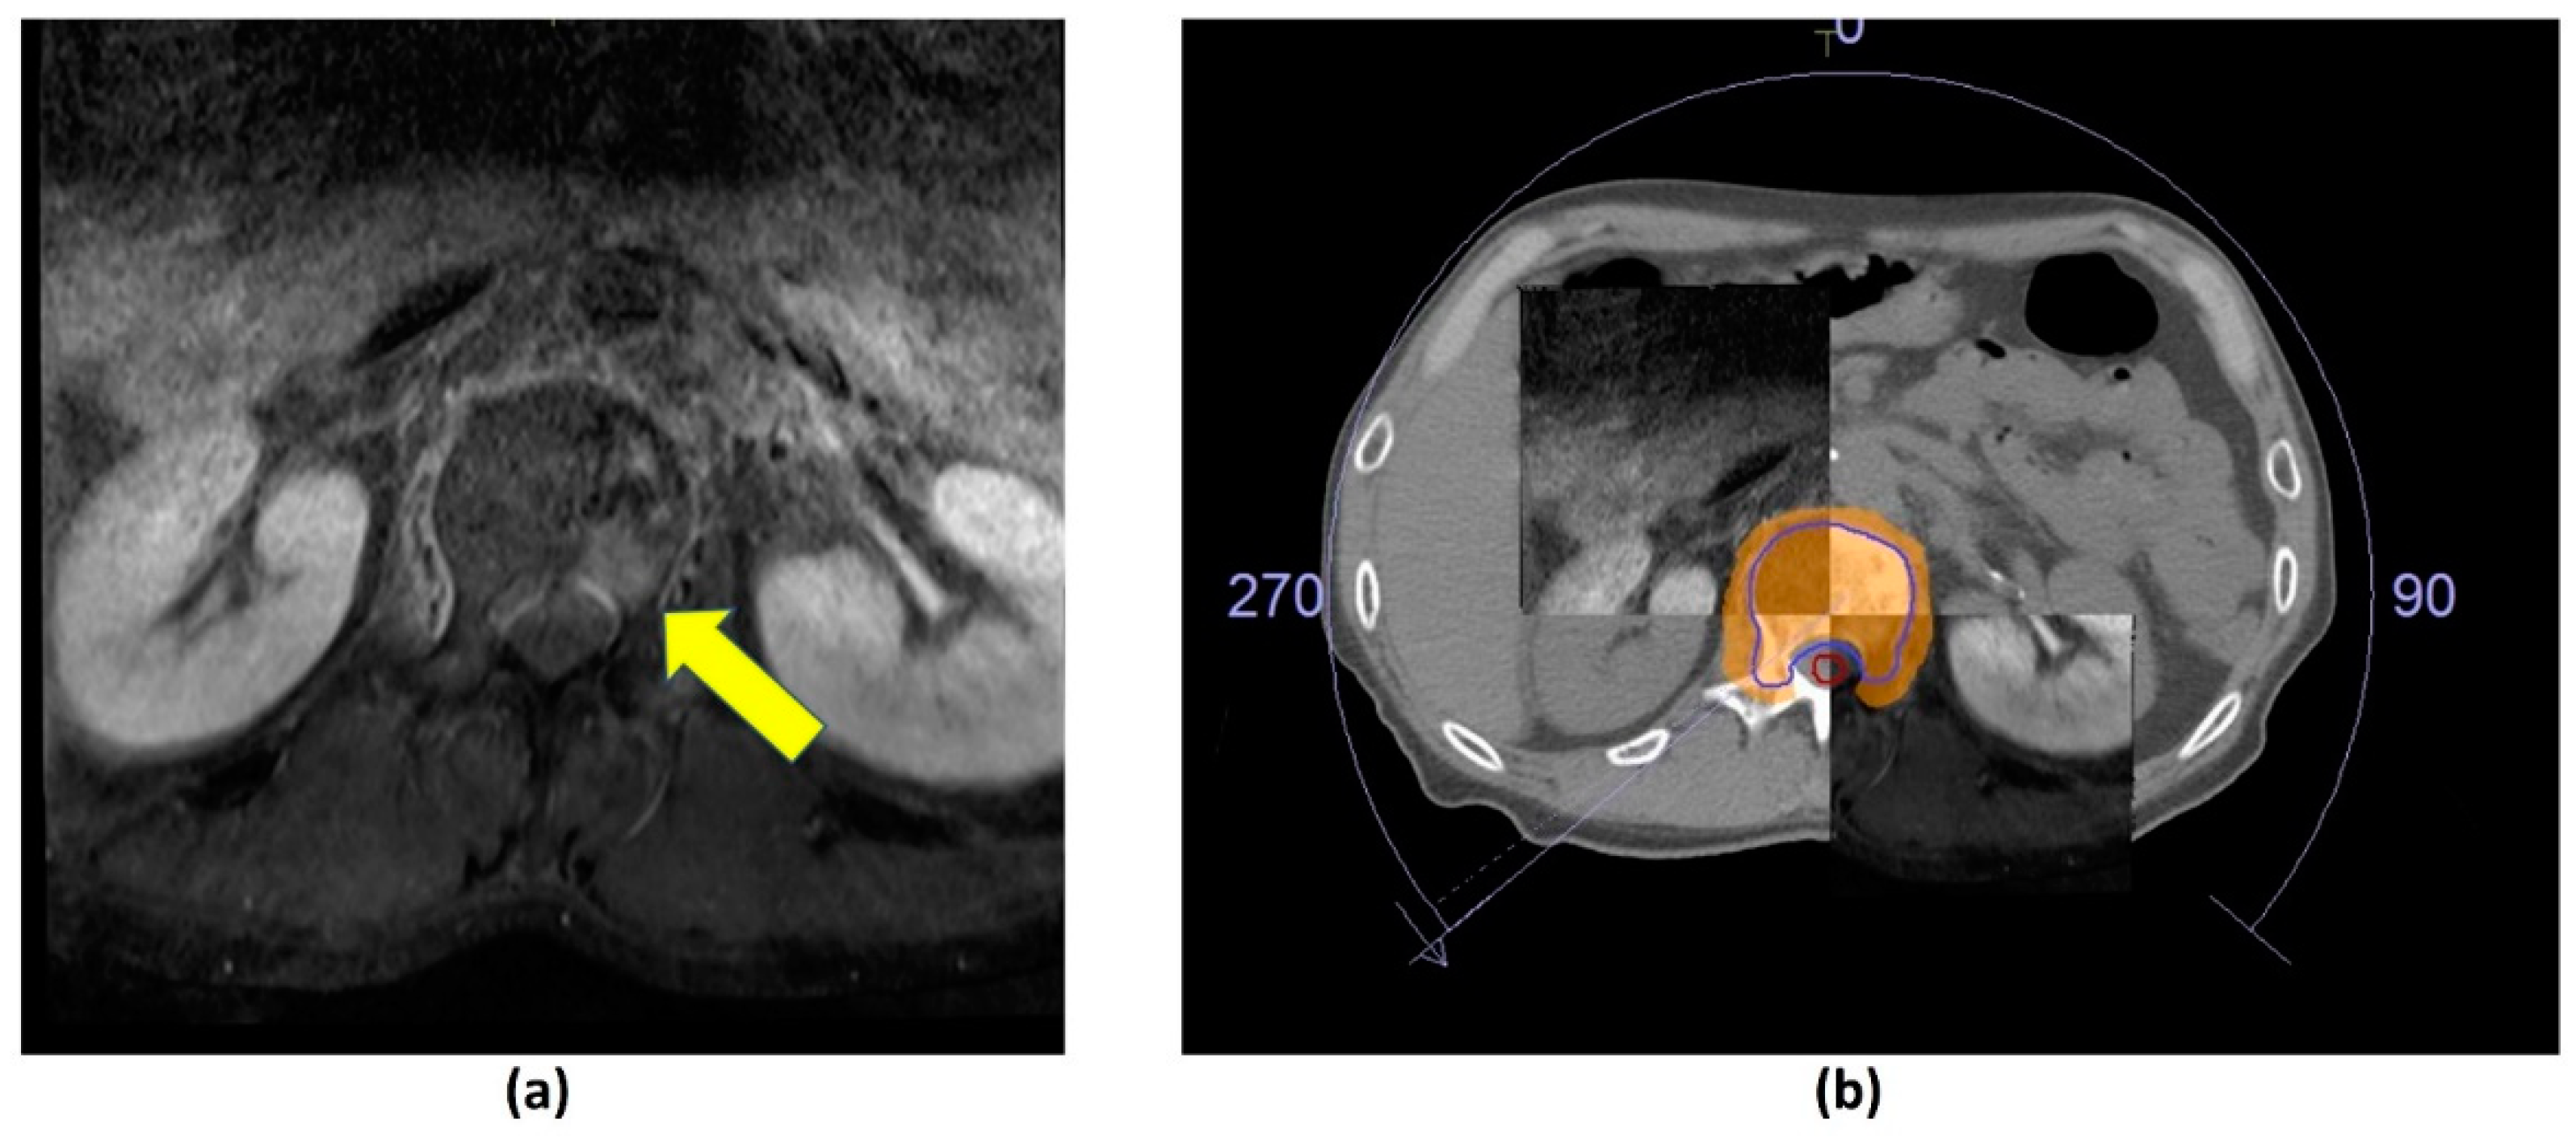

- Jabehdar Maralani, P.; Lo, S.S.; Redmond, K.; Soliman, H.; Myrehaug, S.; Husain, Z.A.; Heyn, C.; Kapadia, A.; Chan, A.; Sahgal, A. Spinal metastases: Multimodality imaging in diagnosis and stereotactic body radiation therapy planning. Future Oncol. 2017, 13, 77–91. [Google Scholar] [CrossRef]

- Mossa-Basha, M.; Gerszten, P.C.; Myrehaug, S.; Mayr, N.A.; Yuh, W.T.; Jabehdar Maralani, P.; Sahgal, A.; Lo, S.S. Spinal metastasis: Diagnosis, management and follow-up. Br. J. Radiol. 2019, 92, 20190211. [Google Scholar] [CrossRef]

- Das, I.J.; McGee, K.P.; Tyagi, N.; Wang, H. Role and future of MRI in radiation oncology. Br. J. Radiol. 2019, 92, 20180505. [Google Scholar] [CrossRef] [PubMed]

- Schmidt, M.A.; Payne, G.S. Radiotherapy planning using MRI. Phys. Med. Biol. 2015, 60, R323–R361. [Google Scholar] [CrossRef] [PubMed]